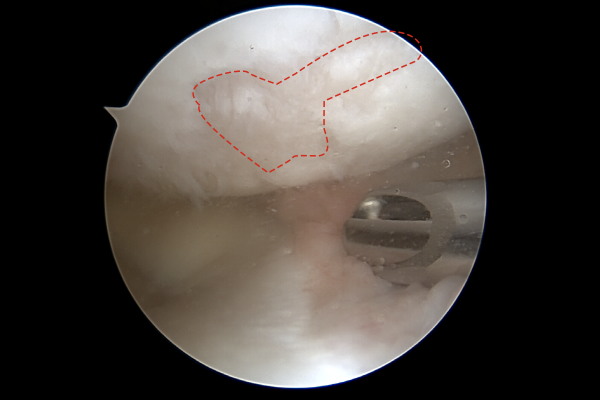

또한 무릎 관절 연골의 손상도 확인되었고,